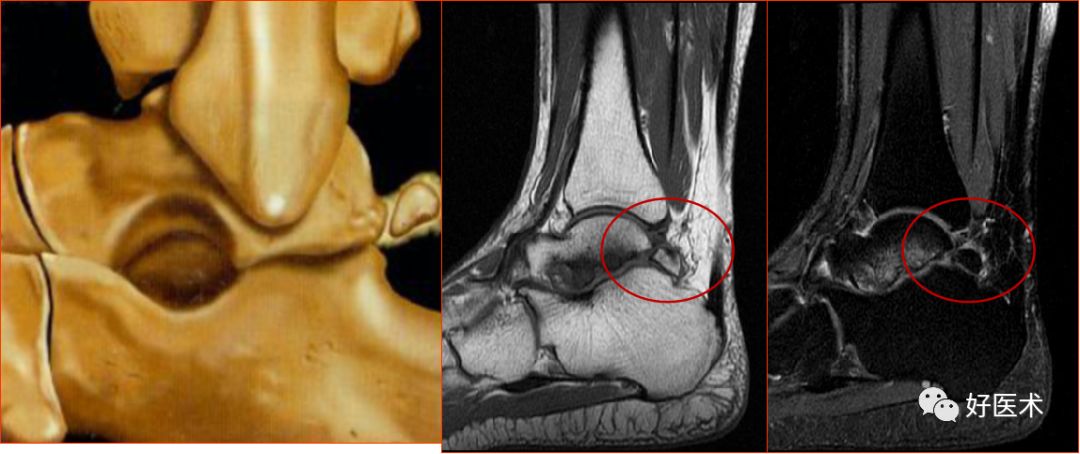

距骨骨缺血坏死,胫骨骨梗死